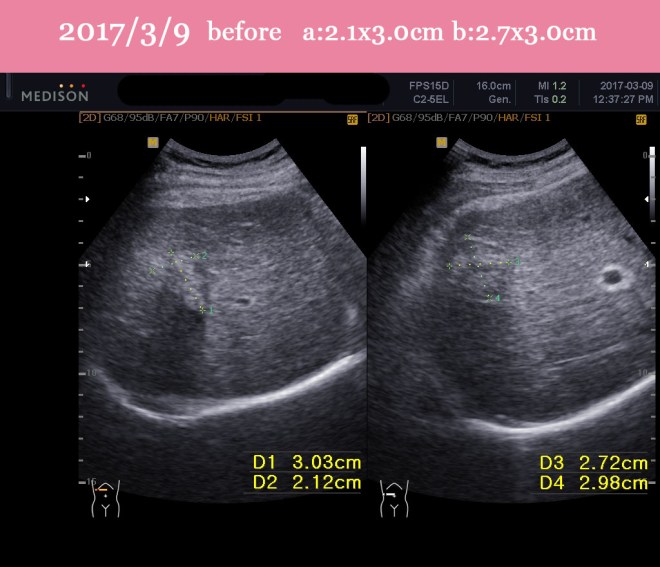

- 2017년 3월 9일 반룡인수한의원 내원 약 3cm의 종양 두개 보임. 한방치료 시작

- 2017년 5월 18일 두개의 종양 중에 하나는 소실됨. 또 하나는 면적대비 58 %로 감소됨

| 2017/3/9 | 강남 영상의학과 초음파 검사. S8. 2.1x 3.0cm S5 2.7x 3.0cm(WXD) | 초음파 검사 |

- 치료 시작 전 (2017/3/9) ABDOMINAL SONOGRAM :

- Known HCC, post-TACE state

- 2.1×3.0cm(WxD, S8) and 2.7×3.0cm(WxD,S5) sized irregular hyperechoic lesions in the right hepatic lobe, compatible with HCC